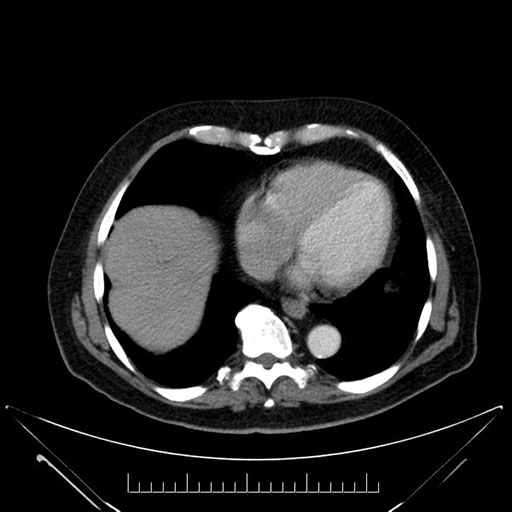

Axial - 3 months prior